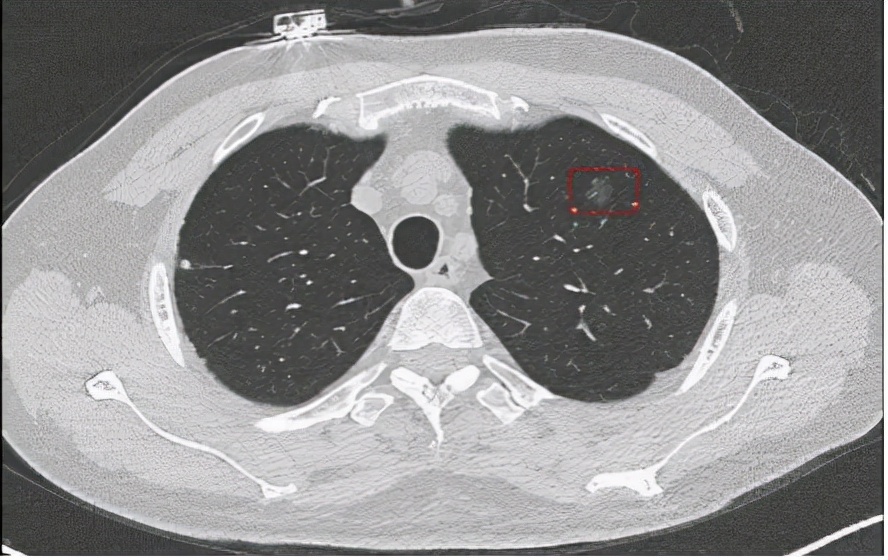

【疾病类型】肺癌cT1aN0M0 Ia1期

这位患者姓李,是云南人,在浙江省一个餐饮店里边当厨师,最近这两个月以来没有什么食欲,一个月前体检发现左肺有结节,并且有23年的抽烟史,平均一天一包,不喝酒也没有肺癌家族史,来我院就诊时患者的面色较差,因为他说好久没正常吃饭了,没有什么胃口,在看了患者自带的肺部CT片子后我考虑患者可能是肺癌,于是为患者办理入院。

入院后我为患者完善了相关实验室检查,实验室检查提示为肺癌。于是在CT引导下经皮肺穿刺活检病理结果为左上肺恶性肿瘤。完善全身PET-CT检查后并未发现肺癌有转移,根据上述发现,临床分期为cT1aN0M0 Ia1期。

术后病理报告:左上肺结节处肺原位腺癌,伴微浸润(浸润灶最大径约0.2cm) 未侵及脏层胸膜,手术标本吻合钉切缘未见癌累及,最大径0.6cm。病理报告:找到(第5组)淋巴结1个、(第9组) 淋巴结1个,均未见癌转移。